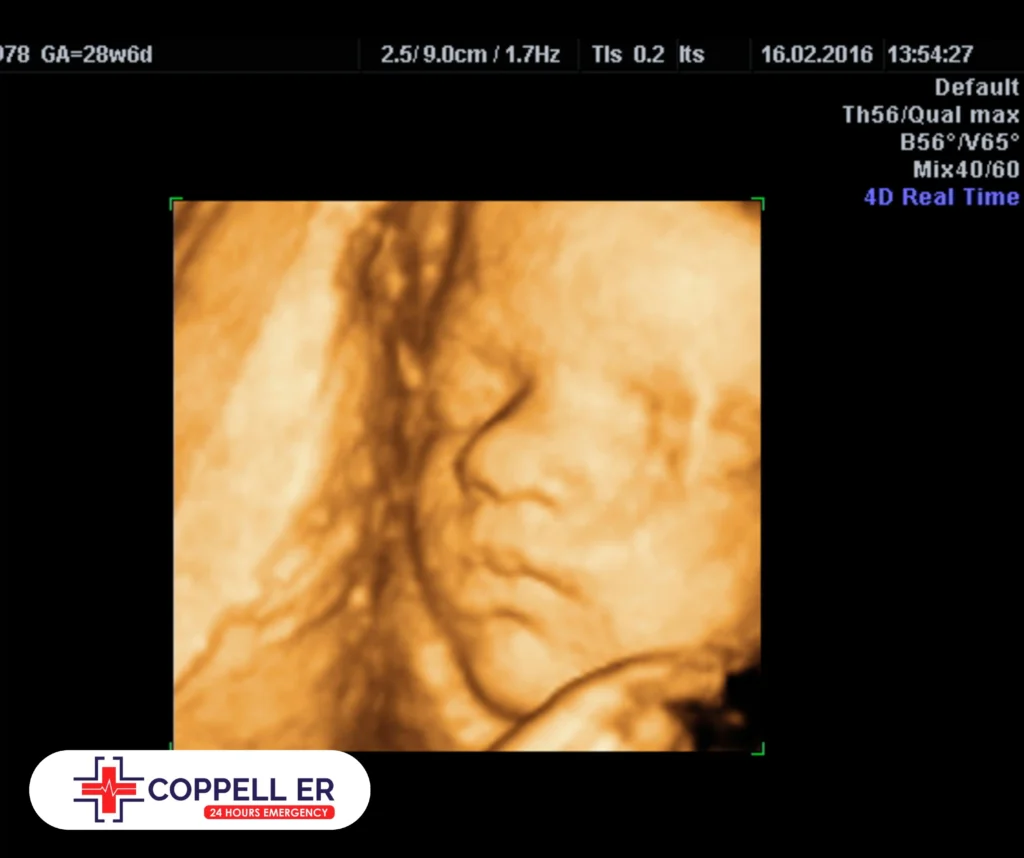

Abdominal ultrasound has become a ubiquitous diagnostic tool in modern medicine, allowing healthcare professionals to visualize and assess various internal organs in real-time. A standard abdominal ultrasound exam requires a thorough understanding of the technical requirements and diagnostic criteria.

High-frequency ultrasound waves (> 10 MHz) allow for more detailed imaging of superficial structures, like the liver and kidneys. This high-resolution imaging helps identify tiny lesions, such as tumors or liver cysts, that might not be visible with lower frequencies. Furthermore, techniques like B-mode ultrasound and power Doppler can enhance diagnostic quality by visualizing blood flow and detecting vascular anomalies.